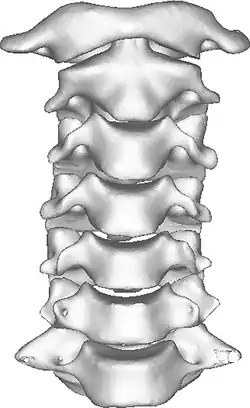

Once there is an onset of the symptoms in the patient, the patients are screened through cervical-spinal imaging techniques: X-ray, CT, MRI. [1] The scanning technique points out any cervical vertebrae defects and misalignments. (Image 1. and 2.) When cervicocranial syndrome is caused as a result of a genetic disease, then family history and genetic testing aid in making an accurate diagnosis of cervicocranial syndrome.